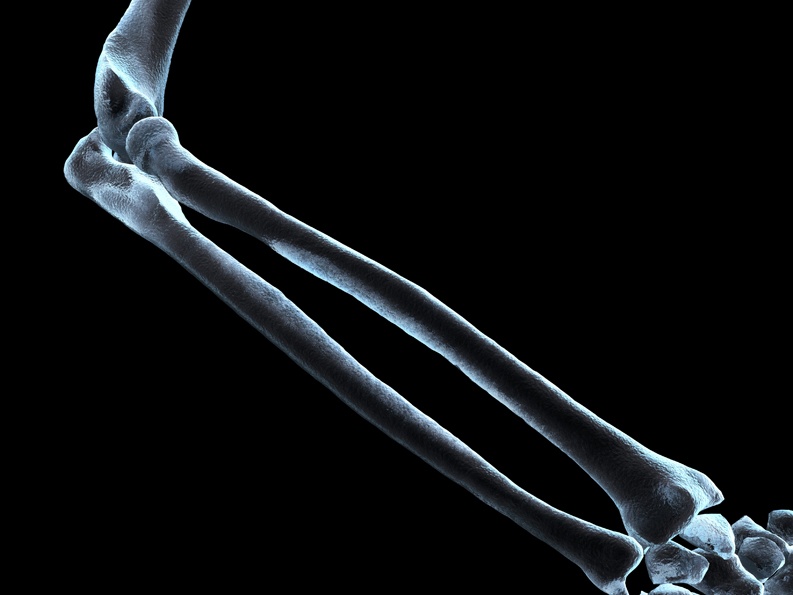

Nepřímé důkazy ukazovaly, že to možné je. Italští patologové z Padovské univerzity již dříve zjistili, že hormon INSL3 ze stejné rodiny jako relaxin může ovlivňovat buňky, které se podílejí na tvorbě kosti. Fyziologická hustota kostí je výsledkem dynamické rovnováhy mezi působením osteoblastů, které kost "stavějí", a jejich protějšku osteoklastů. Tyto buňky odstraňují starou kostní tkáň a svým účinkem tak vyvažují působení osteoblastů. Vědci získali podezření, že relaxin může nějakým způsobem posouvat rovnováhu ve prospěch odbourávání kosti.

Svou hypotézu si teď potvrdili na kulturách lidských buněk. Relaxin se navázal na receptory osteoklastů, a tím je přiměl "hladově" vstřebávat kostní tkáň. Buňky stimulované relaxinem nakonec do kosti vyžraly velké díry a do svého okolí uvolnily velké množství vápníku. Vzestup hladiny vápníku neboli hyperkalcémie je jedním z příznaků kostních metastází. Experimenty také ukázaly, že kromě poškozování kostí relaxin podporuje růst nádorů a způsobuje jejich vyšší invazivitu. Dobrá zpráva je, že tyto účinky ustaly poté, co vědci k buňkám přidali protilátky proti relaxinu. Podle autorů studie je proto možné, že podávání protilátek může zabránit poškození kostí a hyperkalcémii.